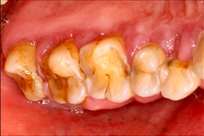

A 65-year-old female on antihypertensives and immunosuppressants presented with severe gum swelling, inability to chew, and difficulty maintaining oral hygiene. This led to multiple decayed and periodontally compromised teeth, worsening her overall condition.

Drug-influenced gingival overgrowth or ‘DIGO’ in short, manifests as abnormal swelling of the gingiva.

- The condition is usually caused by adverse reactions to certain drugs such as antihypertensives, anticonvulsants or immunosuppressants.

- As the gum tissues become significantly larger, it may impede normal masticatory function, daily oral hygiene, and aesthetics, severely diminishing one’s quality of life. (Sabarudin et al. 2022)